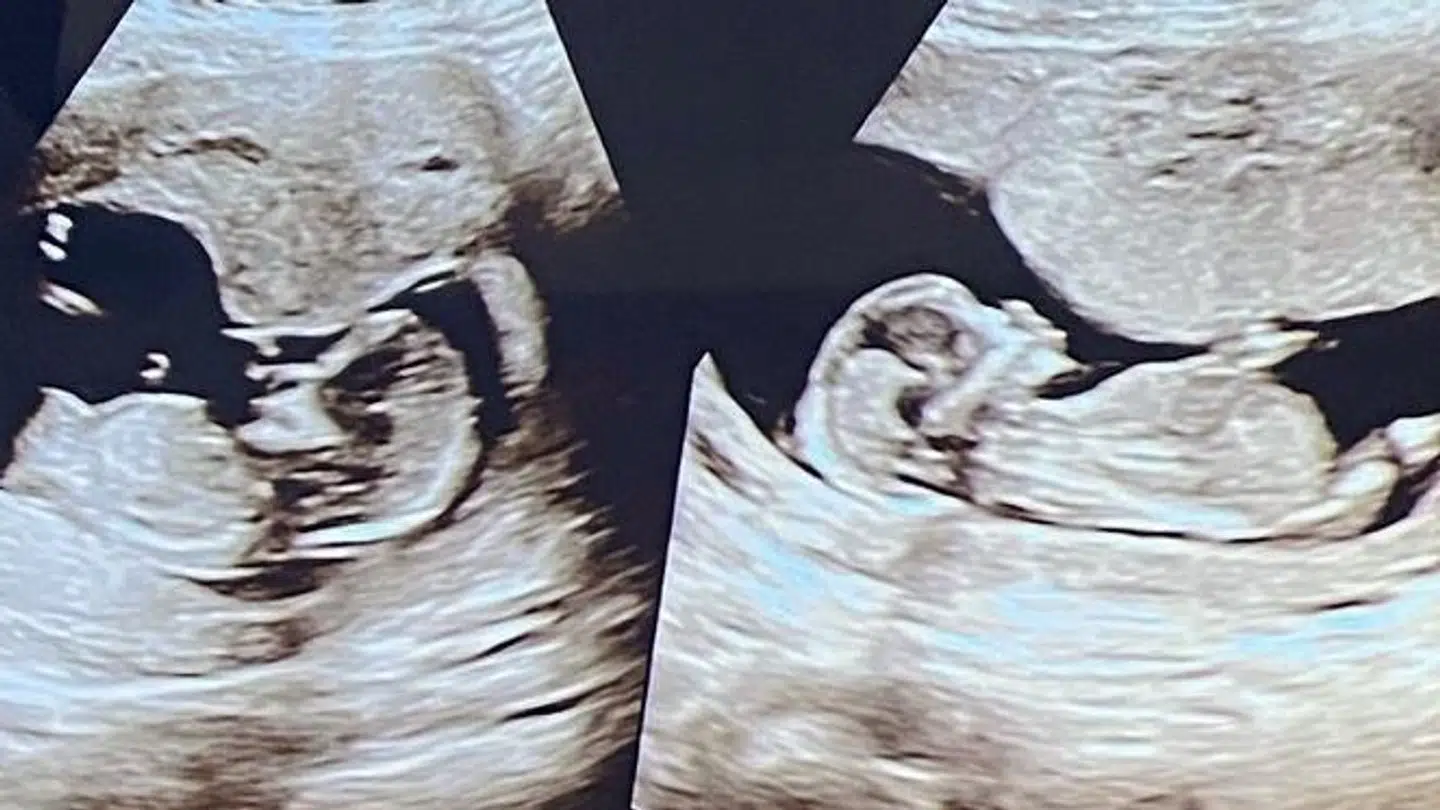

Sådan fortæller Dennis Knudsen til B.T. om de to tvillingepiger, han venter sig med en ny rugemor til september.

Hans nye rugemor fik så lagt to æg op for at øge sandsynligheden for en graviditet, og så endte det, som Dennis Knudsen havde håbet: Begge æggene blev befrugtet.